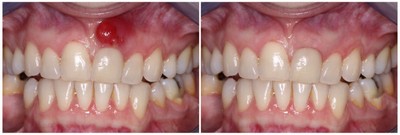

Со свищом

Свищ чаще всего развивается при гранулирующей форме патологии, из-за разрастания грануляций происходит формирование дефекта, разрушаются окружающие ткани.

Если образуется свищ, то это свидетельствует о том, что лечение не действует и микроорганизмы продолжают разрушать зуб.

Терапия заключается в следующем:

- Очистка полости зуба и его каналов.

- Обработка антисептиком.

- Пломбирование зубной полости.

Одонтогенный свищ лечится не за одно посещение врача. Терапия такого заболевания протекает легче из-за возможности оттока продуктов воспаления через свищевой ход.